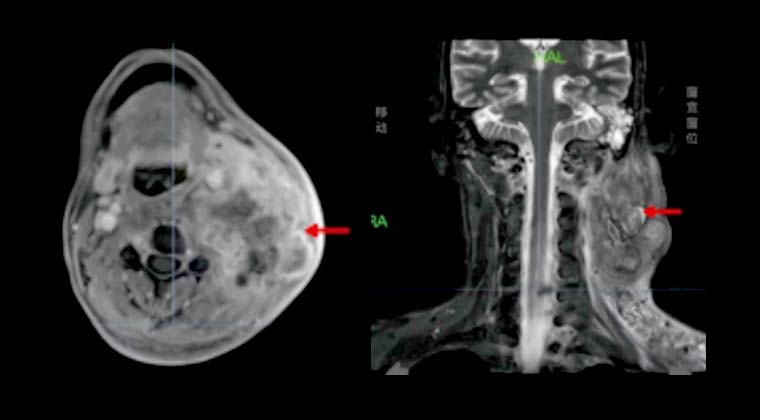

② Случай 2:

Пациент: Мужчина, 47 лет

Диагноз: Злокачественная опухоль носоглотки (дифференцированная неороговевающая карцинома носоглотки, cT4N3M1, стадия IV)

Симптомы: Периодическое головокружение, сухость во рту, жажда, полиурия

30.12022 - проведена радиотерапия TOMO

Дозы облучения: PGTV 69,96 Гр / 2,12 Гр / 33 фракции, PTVn 66 Гр / 33 фракции, PTV 60 Гр / 33 фракции

Через 3 месяца после лечения при визуализации отмечалось значительное уменьшение размеров и числа множественных метастазов в шейных лимфоузлах.

До лечения:

После лечения: